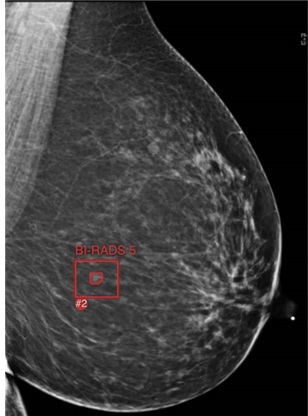

Il tumore al seno rappresenta il 25% di tutti i nuovi casi di tumore e costituisce la principale causa di morte per cancro (15,5%) nella popolazione femminile. Lo screening mammografico riduce la mortalità per tumore al seno del 20-31% tuttavia presenta dei limiti che ne riducono l’efficacia, infatti la sensibilità della metodica scende fino al 48% nei seni densi e nei programmi di screening è stimato circa il 10-20% di falsi positivi. L’utilizzo dell’intelligenza artificiale (IA), guidata principalmente dal deep learning e dalle reti neurali convoluzionali, applicata allo screening mammografico sta rivoluzionando il campo della radiologia senologica. L’IA come strumento di controllo qualità standardizzato migliora l’accuratezza della diagnosi delle patologie mammarie ed è stato recentemente dimostrato un impatto significativo del suo utilizzo nello screening mammografico, fino a un aumento del 29% nella rilevazione dei tumori al seno. Le macro applicazioni dell’IA nello screening mammografico sono: Analisi delle immagini che rileva e classifica in maniera automatica le lesioni; Segmentazione delle immagini per identificare le aree di interesse; Supporto decisionale ai radiologi; Miglioramento della qualità dell’immagine con una riduzione del rumore ed un aumento della risoluzione. La presenza di microcalcificazioni, composte da fosfato di calcio e ossalato di calcio e la cui deposizione avviene tramite un processo cellulare attivo o per degenerazione cellulare, porta alla diagnosi di tumore non palpabile fino al 55% dei casi. La valutazione mammografica delle microcalcificazioni presenta una bassa specificità, che varia dal 10% al 60% e il numero di biopsie non necessarie a causa di risultati falsi positivi è elevato. L’ ASST Fatebenefratelli-Sacco ha avviato una valutazione di tipo value based healthcare dei software di IA disponibili a supporto della radiologia senologica e per lo screening mammografico. Tali software sono in grado di indagare il potenziale di una rete neurale convoluzionale profonda (dCNN) per classificare accuratamente le microcalcificazioni nelle mammografie e ottenere un sistema di classificazione standardizzato e indipendente dall’osservatore, basato sul catalogo del Breast Imaging Reporting and Data System. L’obiettivo dell’utilizzo del dCNN come strumento di controllo qualità standardizzato è migliorare l’accuratezza diagnostica riducendo così i falsi positivi e consentendo una riduzione dei costi e dei tempi di attesa.